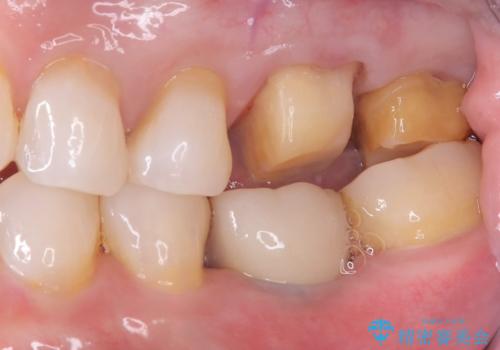

- 主訴:詰め物と歯の奥が側の境目に物がいつも溜まってしまう

保険適応のメタルインレーと歯質との間に不適合な箇所を認め、補綴物のやり替えでの治療となりました。インレーからクラウンへ補綴物の形態を変更し、素材は清掃性・適合性・審美性の点からセラミッククラウンでのやり替となりました。

レントゲン上にて、左上6番遠心にインレーと歯質の不適合を認めます。

健全歯質の残存量から、クラウンでのやり替えを提案しオールセラミッククラウン(スタンダード)でのやり替えとなりました。

・オールセラミッククラウン(スタンダード) 121,000円(税込み)

・仮歯 11,000円(税込み)